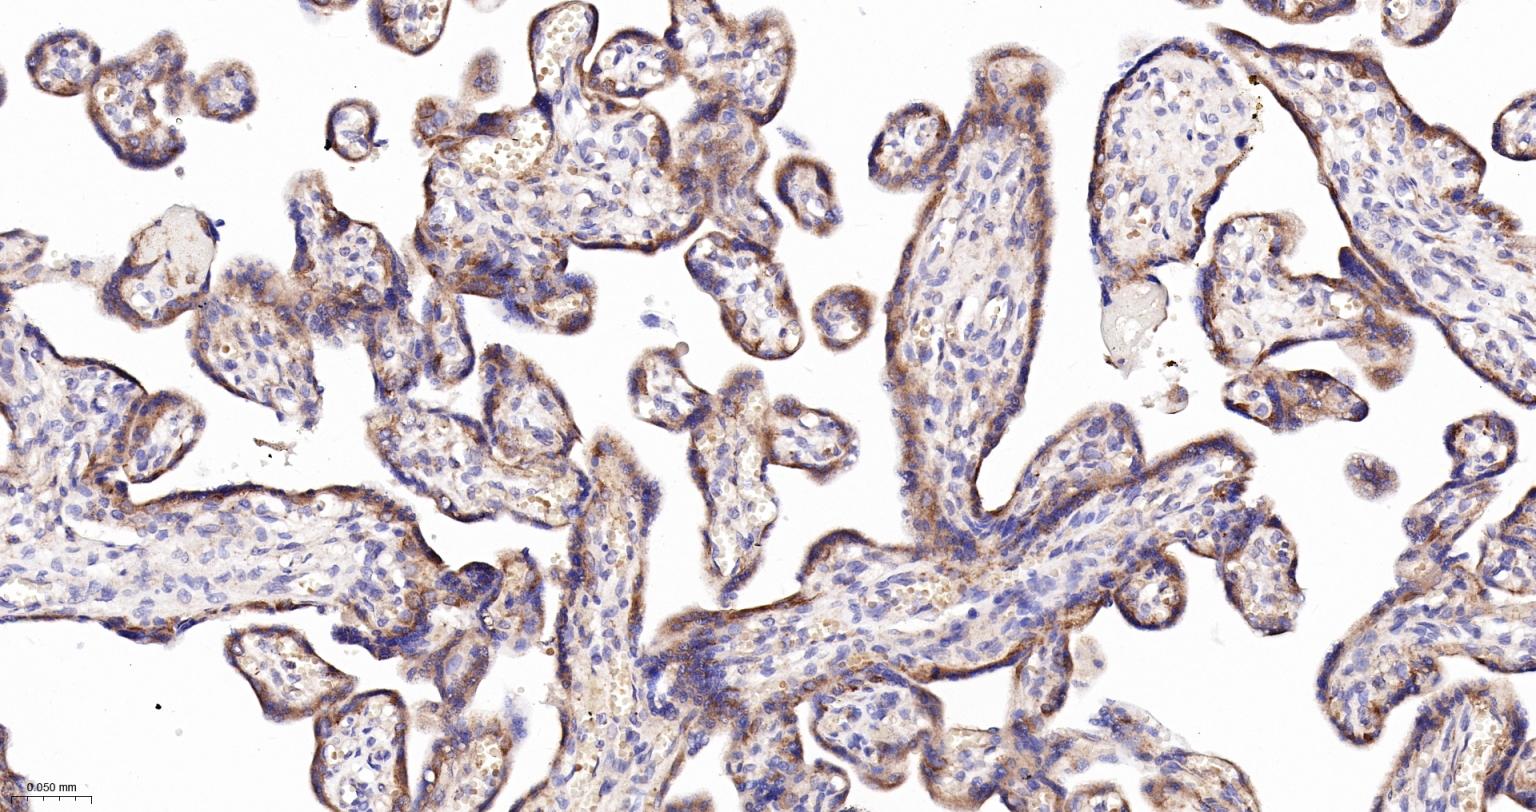

Paraformaldehyde-fixed, paraffin embedded Human Placenta; Antigen retrieval by boiling in sodium citrate buffer (pH6.0) for 15 min; The section was incubated with VAMP8 Monoclonal Antibody, Unconjugated (bsm-61388R) at 1:200 overnight at 4°C, followed by conjugation to the bs-0295G-HRP and DAB (C-0010) staining.